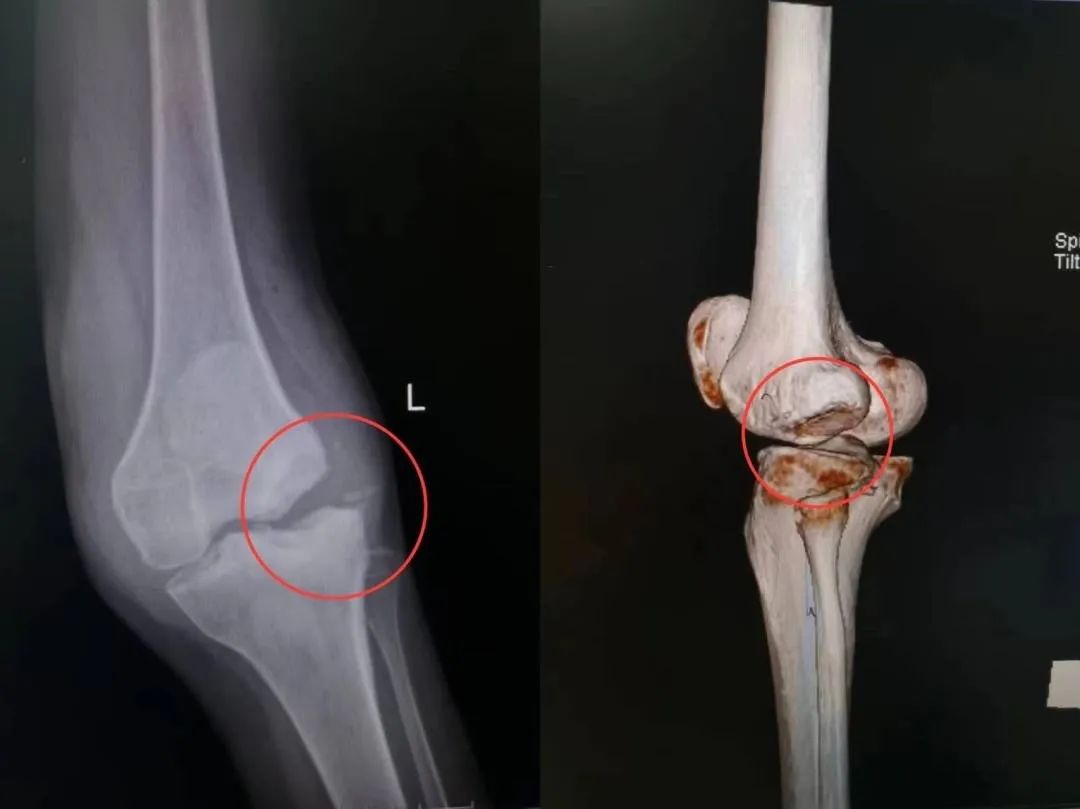

在亲友的介绍下,陈大姐来到了岳阳市中心医院关节外科张彦主任的门诊。张彦主任检查发现陈大姐存在严重的骨破坏和关节肿胀,由于病情进展过于迅速,该疾病具有迷惑性和复杂性,高度怀疑神经性骨关节病,还需要进一步的检查和诊断。“不痛,能走能干活就行”,这是陈大姐的简单诉求。但对于张彦来说,要同时解决疼痛并矫正畸形,才是医者给患者最佳的治疗方案。“除了解决她的膝关节疼痛,还要尽量想办法让她行动自如,来住趟院非常不容易。”通过仔细的查体、详实的影像学检查,诊断明确——神经性关节病。从患者的基础疾病、承受能力、心理想法,到患者的家庭经济、期望值等,张彦都进行了全面的了解,考虑到由于患者股骨远端、胫骨近端大量骨质缺损,膝关节软组织极不稳定,采用常规的人工膝关节假体难以重建膝关节线、保证膝关节的稳定性和活动度。经过仔细斟酌后,团队最终决定为陈大姐实施定制的手术方案——旋转铰链式。在与张主任的沟通和相处的过程中,陈大姐和家人更加信任,欣然接受了这难度与挑战极大的手术。